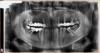

SergeiVar Опубликовано 31 августа, 2013 Поделиться Опубликовано 31 августа, 2013 Пациенту 47 лет.Беспокоит пульпит 28 зуба.Ортопедия была лет 8-10 назад. Сделали оптг, а там кисты. Я затрудняюсь составить план лечения. Подскажите. Ссылка на комментарий

IvanK Опубликовано 1 сентября, 2013 Поделиться Опубликовано 1 сентября, 2013 Удалил бы 18, 48,47, 45 (простите меня, терапевты ), 28,38Повтороное лечение : 13, 23, 25, 27Пародонтологическое лечениеОртодонтическое лечение протезирование с опорой на имплантаты 2 Ссылка на комментарий

Чертков Александр Опубликовано 2 сентября, 2013 Поделиться Опубликовано 2 сентября, 2013 Удалил бы 18, 48,47, 45 (простите меня, терапевты ), 28,38Повтороное лечение : 13, 23, 25, 27Пародонтологическое лечениеОртодонтическое лечение протезирование с опорой на имплантатыРасширение плана Ивана.Если на орто не пойдет, то еще и 3.4, 3.5, 3.7 на выходТотальная реабилитация (фронт Пресс, жевательные циркон или мк с опорой на импланты) 1 Ссылка на комментарий

bullbull Опубликовано 3 сентября, 2013 Поделиться Опубликовано 3 сентября, 2013 14, 15, 16 - винты22, 23, 24 - резекция верхушки или на вынос, 27 на вынос. 45, 47 - туда же.Потом в область отсутствующих - винты.3-й сектор - согласен с предыдущими ораторами (или ортодонт или убрать/поставить) Для эконом: поставить в область 14, 24 винты и съемник на них. Ссылка на комментарий

M@estro Опубликовано 3 сентября, 2013 Поделиться Опубликовано 3 сентября, 2013 (изменено) Средний вариант : 1) удаление всех восьмерок и 4.7. 2) Перелечивание опорных зубов. 3) Мезиализация 3.4 ,3.5. ,дистализация 3.7 . 4) имплантация 3.6 ,4.6 ,в последующем можно доставить 4.7 5) протезирование на "и",и перепротезирование в/ч Эконом - вариант : оставить это как есть до Крещенских купаний, а когда полезут свищи - всё причинное удалить и поставить пластинки "на присосках" (тошнит от этой терминологии) . Изменено 3 сентября, 2013 пользователем M@estro Ссылка на комментарий